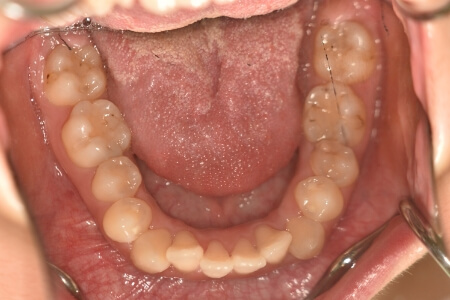

開咬(抜歯)【2245】

初診時

症例 症例 症例 症例

治療内容の詳細 初診時18歳の女性で、前歯がでている事を気にされ来院されました。

検査の結果、開咬を伴うアングルⅡ級1類不正咬合と診断しました。

治療としては、上顎第一小臼歯を抜歯の上、セルフライゲーションブラケット装置(デーモンシステム)とマウスピース型矯正装置(インビザライン)で配列を行いました。顎間ゴムの協力もあり、開咬がきれいに改善されました。

この際、上顎に歯科矯正用アンカースクリューを設置し上顎前歯部後退時の土台としました。